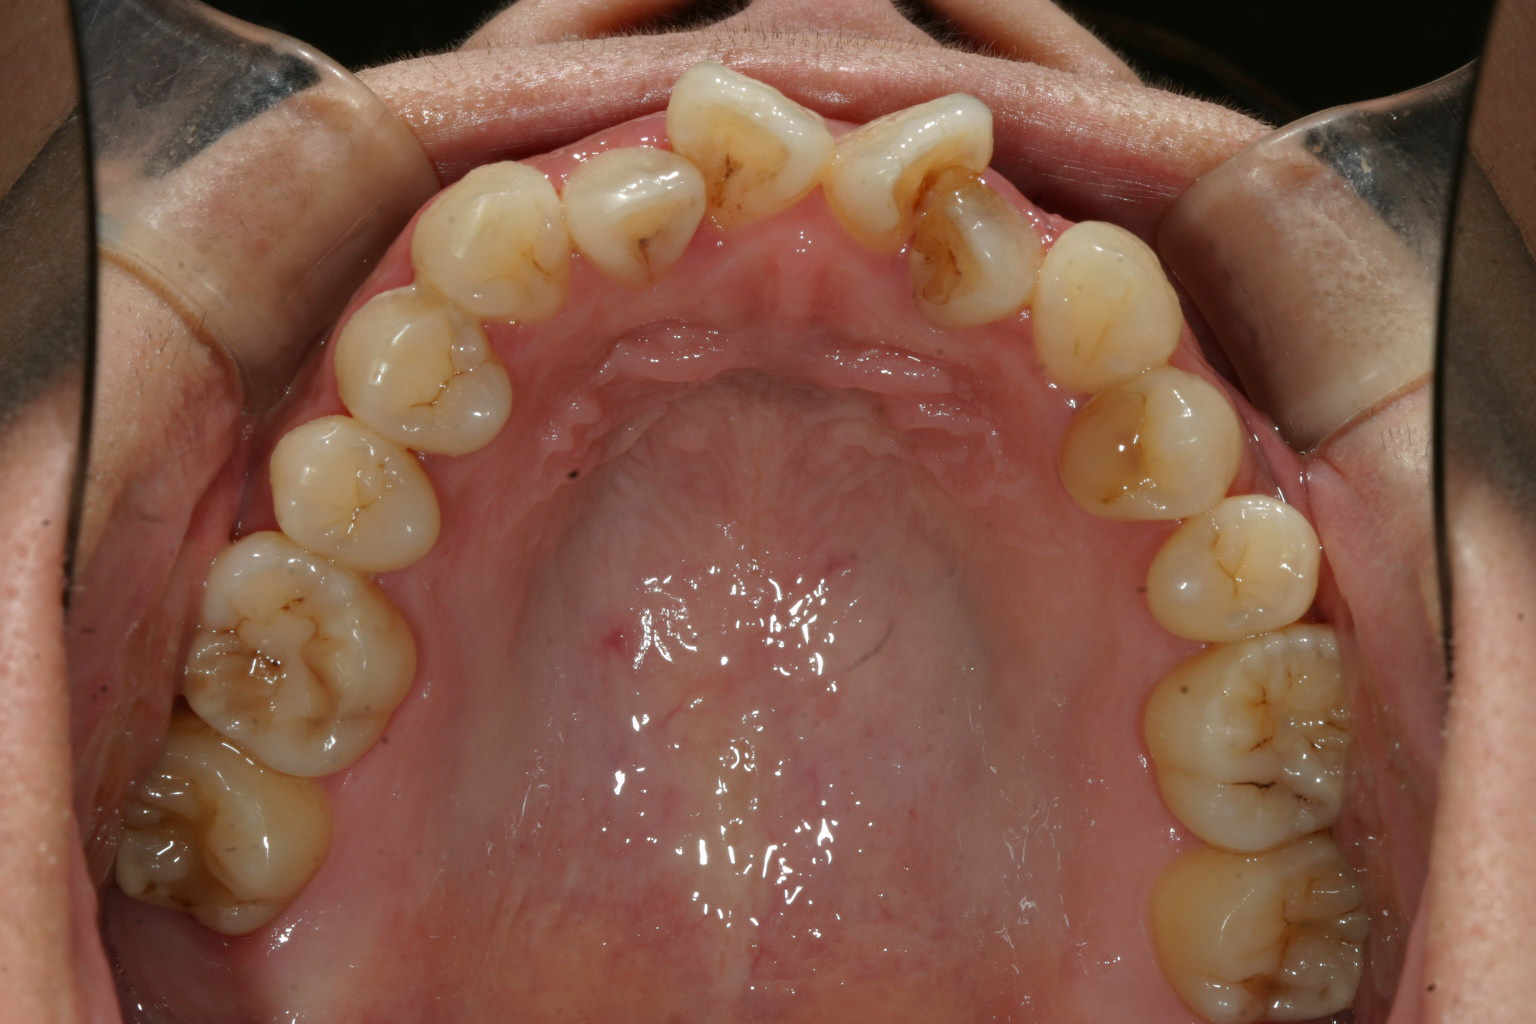

上顎1番が鳥の翼のように反転してますね~この様な症状を翼状捻転って言います。

下顎の症状は軽度ですね~